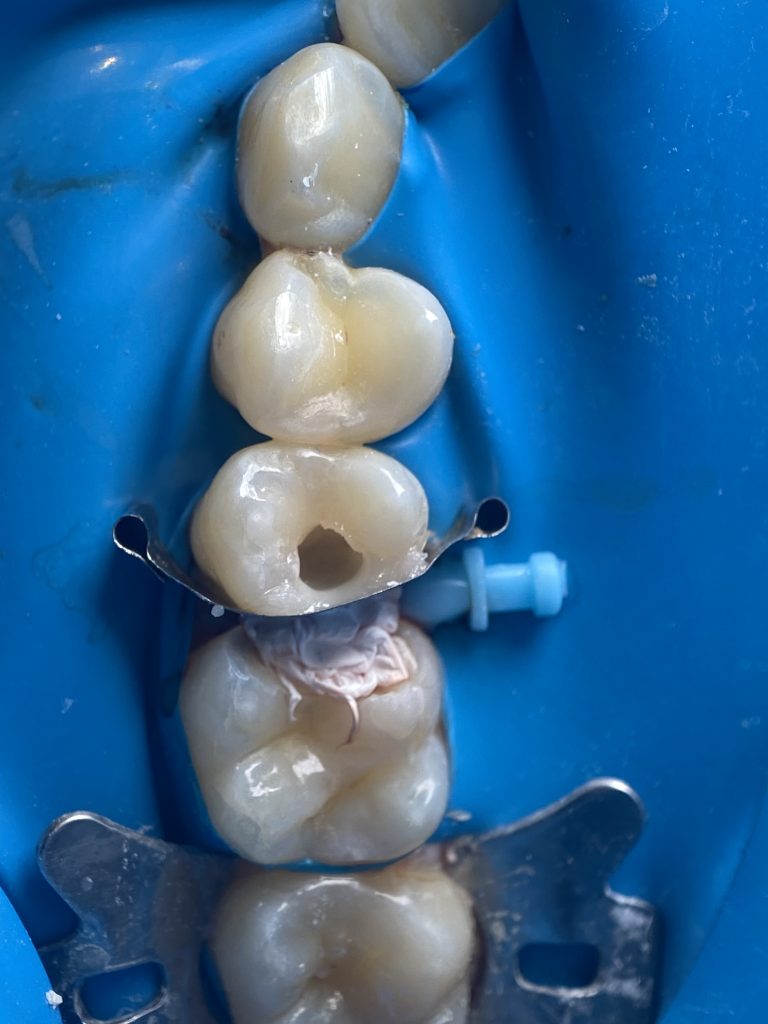

*Completion of the palatal cusp

*The cusp was completed with bulk-fill flowable composite to correctly position the matrix band and prevent the ring from deforming the band and disrupting the emergence profile.